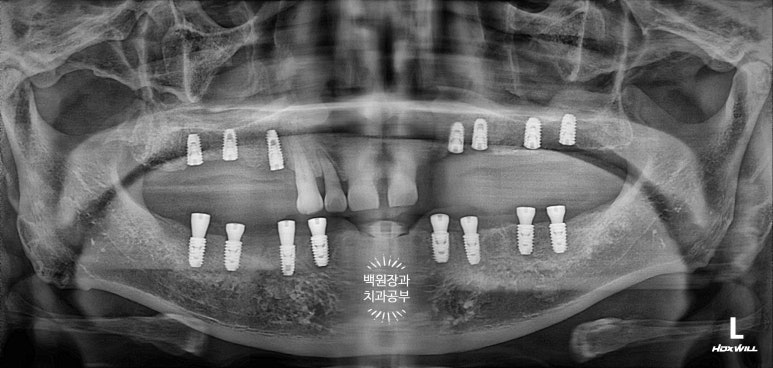

아래는 치아가 하나도 없는 상태셔서... 14개의 치아를 만들어드리기 위해 총 8개의 임플란트를 심어드렸습니다.

센스 있는 분들은 눈치채셨을 수도 있는데, 위 아래의 임플란트가 생긴게 좀 다르죠?

위턱은 잇몸 안에 임플란트가 다 들어가 있는 상태입니다. 뼈이식을 동반하였기 때문입니다.

(뼈이식 재료가 밖으로 쏟아져 나오면 안되잖아요!!)

아래턱의 경우 뼈 상태가 워낙 튼튼하니 좋으셨고, 뼈이식이 많이 필요하지 않아 치유지대주까지 연결해드렸습니다.

즉, 위턱은 임플란트 1차수술까지 진행된 것이고 아래턱은 임플란트 1차수술,2차수술이 한 번에 모두 완료된 상태!